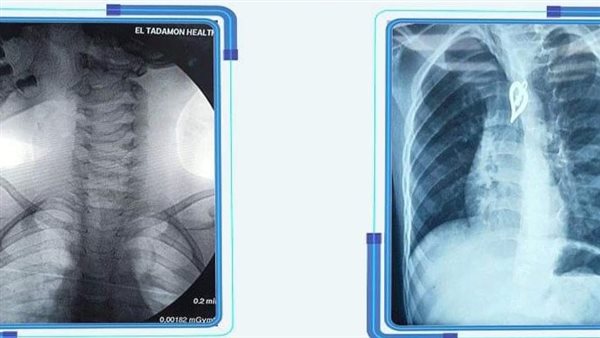

وأكد الدكتور مصطفى شعبان، مدير المستشفى، أن طفلا في الرابعة من عمره وصل لقسم الطوارئ، محولاً من طوارئ مستشفى النصر التخصصي، بعد ابتلاعه جسما معدنيا غريبا "دلاية سلسلة"، حيث ظهرت بالأشعة التشخيصية عالقة بالمريء، وعلى الفور تم مناظرة الحالة وسحب التحاليل والتدخل بجراحة فورية لإنقاذ الحالة.

ونجح الفريق الطبي في استخراج الجسم المعدني بواسطة منظار المعدة الخاص بالأطفال بالمستشفى الذي وجد عالقًا في منتصف المريء، وتم وضع الطفل تحت الملاحظة حتى الاطمئنان عليه، وأجرى التدخل بالمنظار الأطباء "رامي جمال إخصائي الجهاز الهضمي والمناظير، أحمد أمين إخصائي التخدير بالمستشفى".